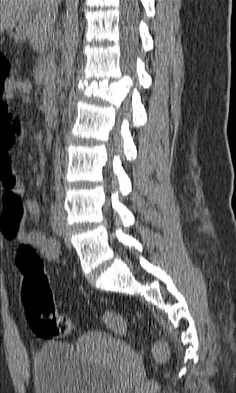

A 12-year-old girl has back pain after falling 20 feet and landing in the sitting position. She has no fractures or other injuries, and her neurologic examination is normal. A lateral radiograph, transverse CT scan, and reformatted sagittal CT scan are shown in Figures 25a through 25c. Which of the following methods is associated with the best long-term outcome?

Explanation

The patient has a displaced burst fracture. Fusion with instrumentation has shown better results than casting alone. Posterior fusion with instrumentation, with sagittal plane correction, yields the best results. Decompression occurs indirectly with correction of the kyphosis. Anterior decompression is unnecessary. Lalonde F, Letts M, Yang JP, et al: An analysis of burst fractures of the spine in adolescents. Am J Orthop 2001;30:115-120. Clark P, Letts M: Trauma to the thoracic and lumbar spine in the adolescent. Can J Surg 2001;44:337-345.

References: